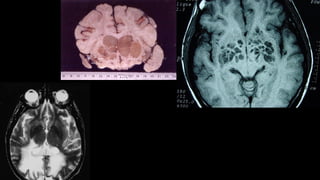

3) Condições que comprometem encéfalo globalmente

(Estruturais)

Algumas causas muito raras:

- Infartos talâmicos bilaterais

- Hematomas Subdurais bilaterais

- Hemorragia subaracnóidea

- Meningite / Encefalite Infarto talâmico Bilateral – Artéria de Pecheron

CAUSA: I- Estrutural Supratentorial

• Infecção:

– Meningites

– Empiemas/ Abscessos

– Neurocisticercose

– Infeccções oportunistas (HIV) – Neurotoxoplasmose, LEMP,

Neurocriptococose

• Metabólico

– encefalopatia de Wernicke

• Desmielinizante

– encefalomielite disseminada aguda

– leucoencefalopatia aguda secundária ao uso de drogas

imunossupressoras e antineoplásicas